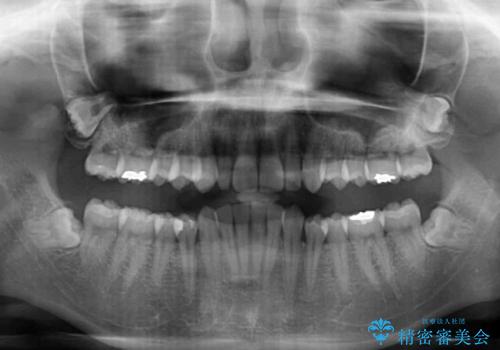

前歯のデコボコと小さい歯を改善 インビザラインとオールセラミッククラウン

- 前歯のデコボコと左右の矮小歯を気にして来院された患者様です。

矮小歯の前後にスペースを作るようにインビザライン矯正治療を計画し、矯正治療後にオールセラミッククラウンによる補綴治療を行うこととしました。

アンカースクリューを用いて上顎歯列全体を後方移動させ、極力過蓋咬合も改善されるよう計画しました。

インビザラインは長時間装着を自己管理する必要がありますが、残念ながら十分な時間の装着を行うことができませんでした。

何とか矮小歯を改善するスペースを作ることはできましたが、過蓋咬合を改善するには至りませんでした。